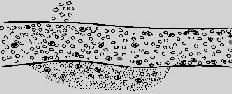

组织受损伤后的微循环很快发生血液动力学变化,即血液的血管口径的改变,病变发展速度取决于损伤的严重程度。血液动力学的变化一般按下列顺序发生(图5-1)。

血管扩张,血流加快

血管进一步扩张,血流开始变慢,血浆渗出

血流变慢,白细胞游出血管外

血流显著变慢,除白细胞游出外,红细胞漏出

图5-1 血液动力学变化模式图